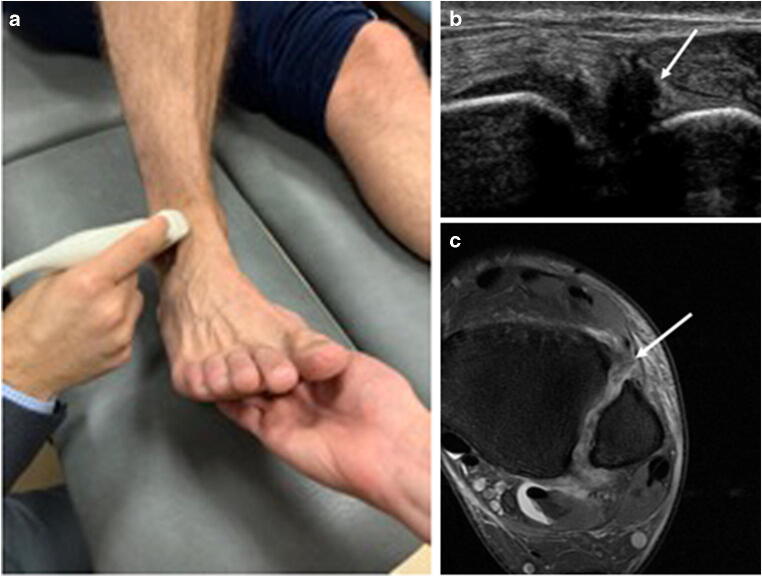

All examinations were performed by the same MSK radiologist (J.A.), with 13 years of experience in MSK ultrasound. An ultrasound device (iU22, Philips) with a high-frequency linear transducer (5–12 MHz) was used for standardised sonographic evaluation. Patients were examined in a supine position with their knees in 90° flexion. Ultrasound of the ATFL was performed by placing the transducer in the transverse plane (longitudinal to the ATFL) anterior to the tip of the lateral malleolus (Fig. 1a). The CFL was visualised with the probe in the frontal plane (longitudinal to the CFL) (Fig. 2a). For visualisation of the anterior tibiofibular ligament, the transducer was placed over the AITFL in the axial plane, about 1 cm proximal to the joint line (Fig. 3a). During the examination of the AITFL, an assistant provided 5–10° passive dorsal flexion of the ankle.

Fig. 1.

Probe position and (US/MR) imaging results for the anterior talofibular ligament (ATFL). Ultrasound for the diagnosis of anterior talofibular ligament (ATFL) injury. a The ultrasound probe is placed in the transverse plane (longitudinal to the ATFL) anterior to the tip of the lateral malleolus. b Ultrasound findings consistent with an intact anterior talofibular ligament (arrow). c Axial PD-FS image showing an intact anterior tibiofibular ligament (arrow)